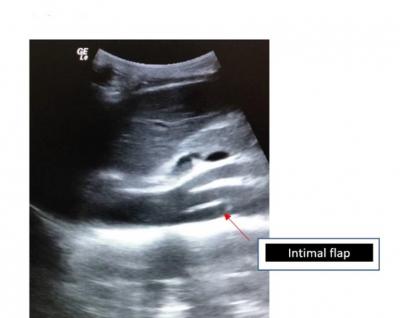

Figure 1: Bedside USG Abdomen in ED shows visualization of an intimal flap (red arrow)